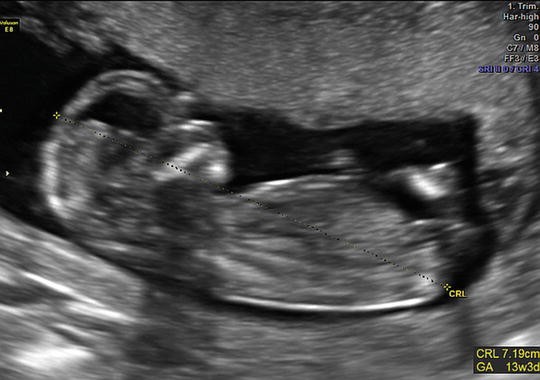

2 . If there is more than one first-trimester scan with a mean sac diameter or crown-rump length measurement, the earliest ultrasound with a crown-rump length equivalent to at least 7 weeks (or 10 mm) should be used to determine the gestational age (III B) . Ideally the dating ultrasound is at least 7 weeks or 10 mm of gestation .

Known conception date using reproductive technologies . 2) Use the earliest ultrasound (TA or TV) estimate if between 7 (CRL > 10 mm) and 22+6 weeks of gestation . 3) First trimester US is the most accurate, so whenever possible, get a dating scan . 4) After 23 weeks, can use US or clinical judgement . 5) Clinical judgement may still be needed, but . . .

ISUOG Guidelines 249 Lambda sign T sign Figure 1 Ultrasound images in the ο¬rst trimester of: (a) a dichorionic diamniotic twin pregnancy, in which the twins are separated by a thick layer of fused chorionic membranes; (b) a monochorionic diamniotic twin pregnancy, in which the twins are separated by only two thin